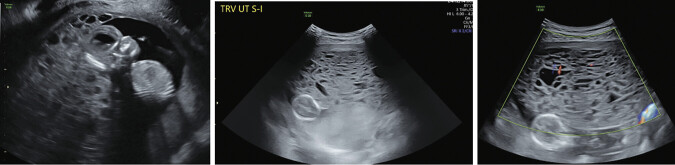

26岁女性,妊娠第1段,妊娠14周1天,出现阴道点滴和全身症状,包括心悸、呼吸短促、热不耐受、恶心和呕吐,持续2周。检查发现产妇心动过速,血压大范围升高,β人绒毛膜促性腺激素2,442,400 mIU/mL升高,促甲状腺激素抑制,T4升高,符合甲状腺风暴,可能伴有严重的先兆子痫。1经阴道超声提示部分臼齿妊娠;这后来被外科病理证实。本病例强调了葡萄胎罕见但严重的并发症,特别是部分臼齿妊娠,包括甲状腺风暴和叠加先兆子痫,强调了在三级保健中心与多学科团队管理的重要性,以优化产妇结局。2 3。

A 26-year-old woman, gravida 1 para 0 at 14 weeks' 1-day gestation, presented with vaginal spotting and systemic symptoms, including palpitations, shortness of breath, heat intolerance, nausea, and vomiting for 2 weeks. Workup revealed maternal tachycardia, severe-range blood pressure, elevated beta human chorionic gonadotropin of 2,442,400 mIU/mL, suppressed thyroid stimulating hormone, and elevated T4, consistent with thyroid storm with possible preeclampsia with severe features. 1 A transvaginal ultrasound suggested a partial molar pregnancy; this was later confirmed by surgical pathology. This case highlights the rare yet serious complications of hydatidiform mole, in particular, a partial molar pregnancy, including thyroid storm and superimposed preeclampsia, emphasizing the importance of management at a tertiary care center with a multidisciplinary team to optimize maternal outcomes. 2 3.